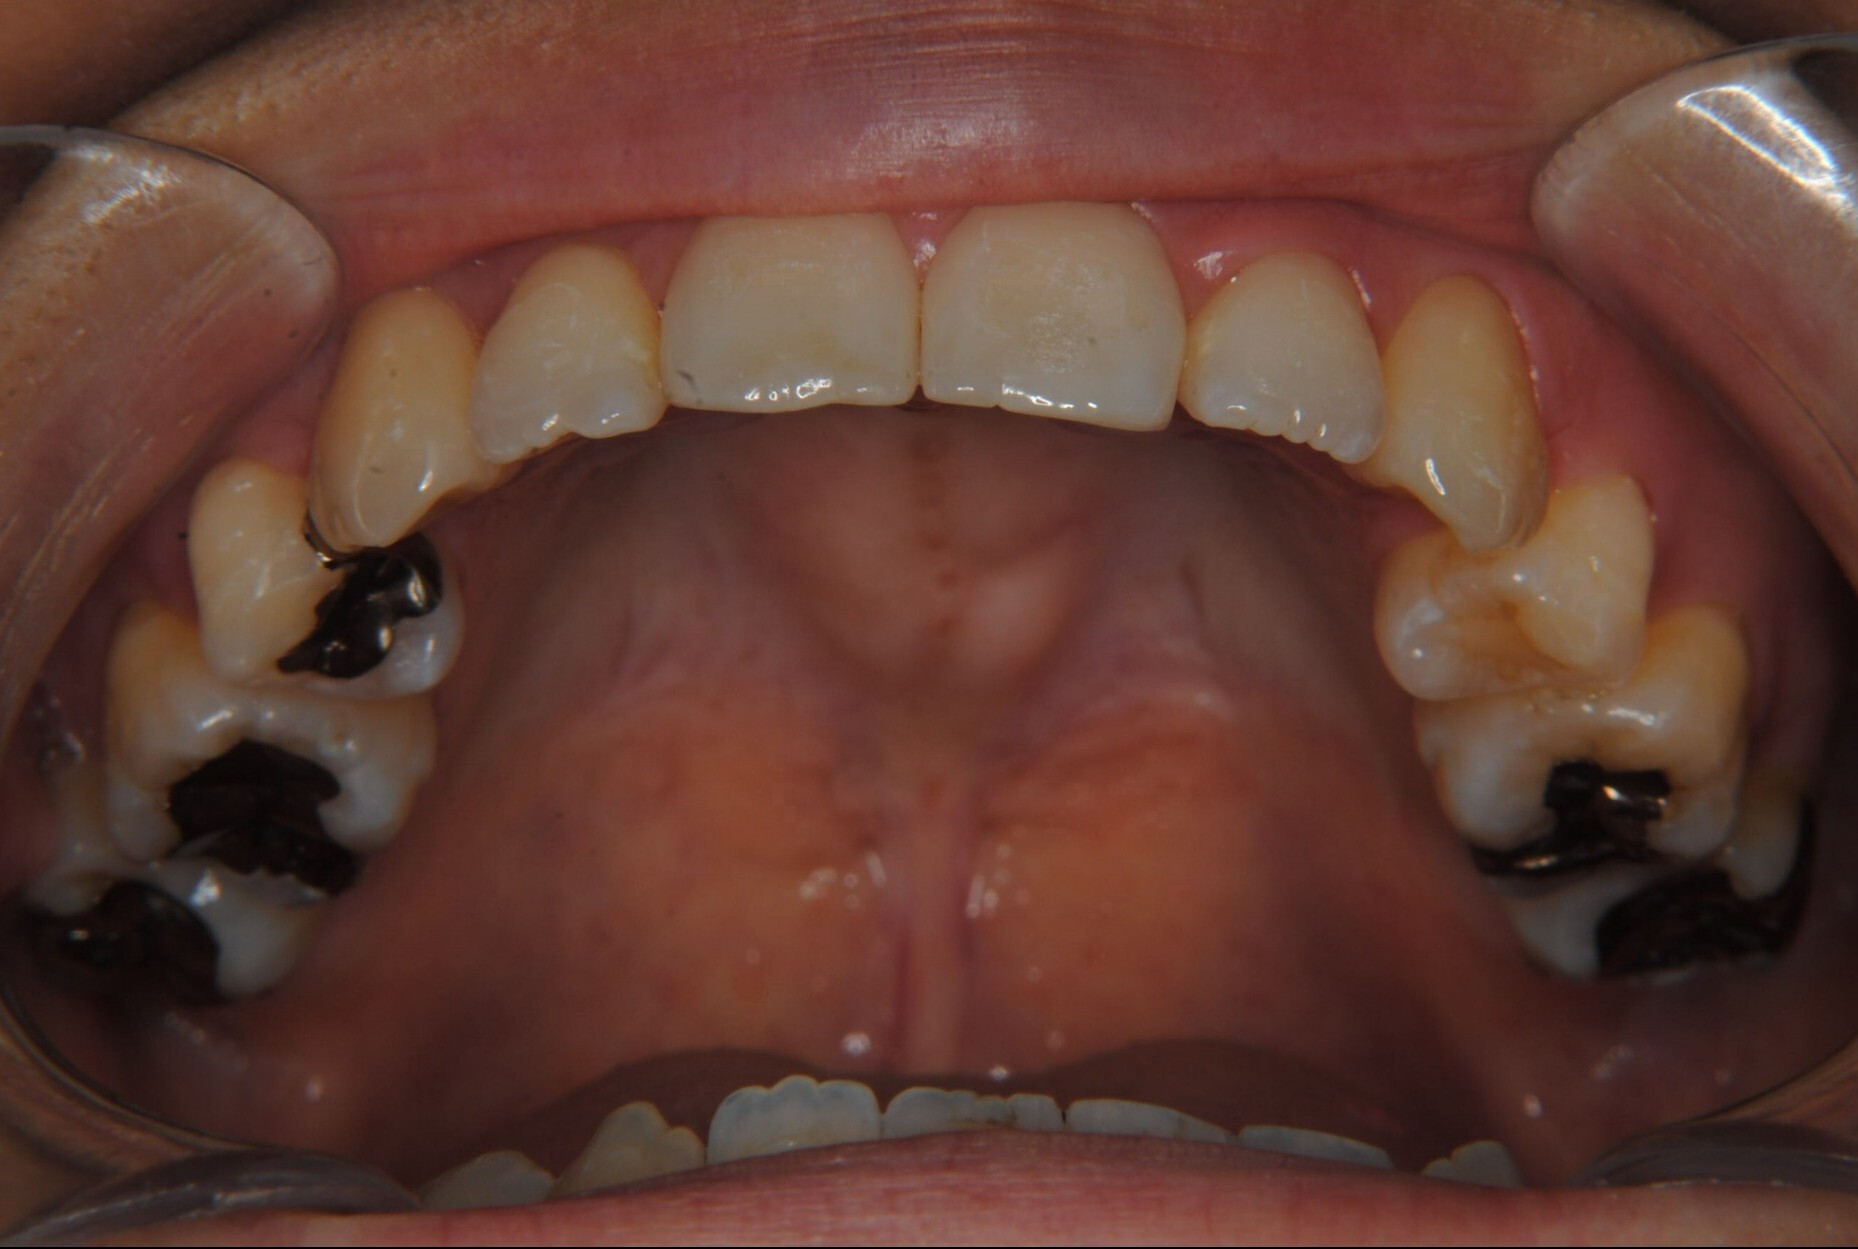

①主訴:八重歯、前歯のガタガタ、真ん中の不一致を治したい

②診断名:AngleⅠ級叢生

④治療に用いた主な装置:マルチブラケット装置(T21ブラケット)

⑤抜歯部位:上下左右第一小臼歯

⑧リスクと副作用:マルチブラケット装置(T21ブラケット)を初めてつけてから4日間、食事の時におもに前歯が少し痛かったとのことでした。治療後のエックス線写真で、歯根吸収はほとんど観察されず、歯肉を診ると残念ながら下顎前歯部に歯肉退縮(ブラックトライアングル)が生じていました。しかし、通常下顎前歯部は下唇に隠れてむき出しにはなっていないので、ご本人はあまり気にされていないご様子でホッとしています。